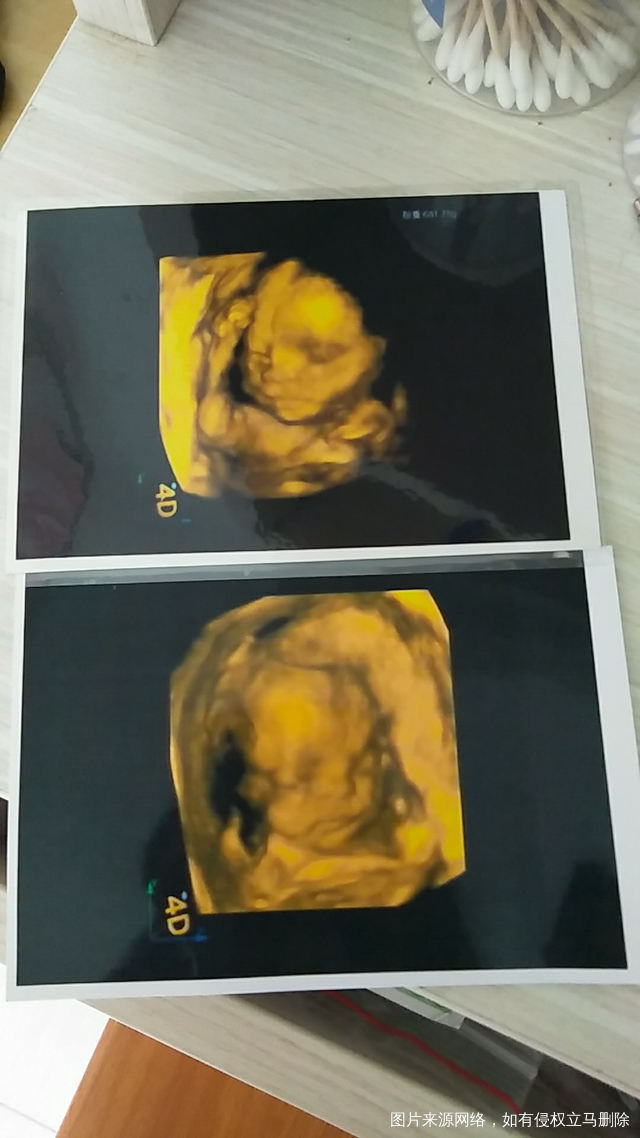

看看肚子里的像不像女儿。第一个是儿子大宝